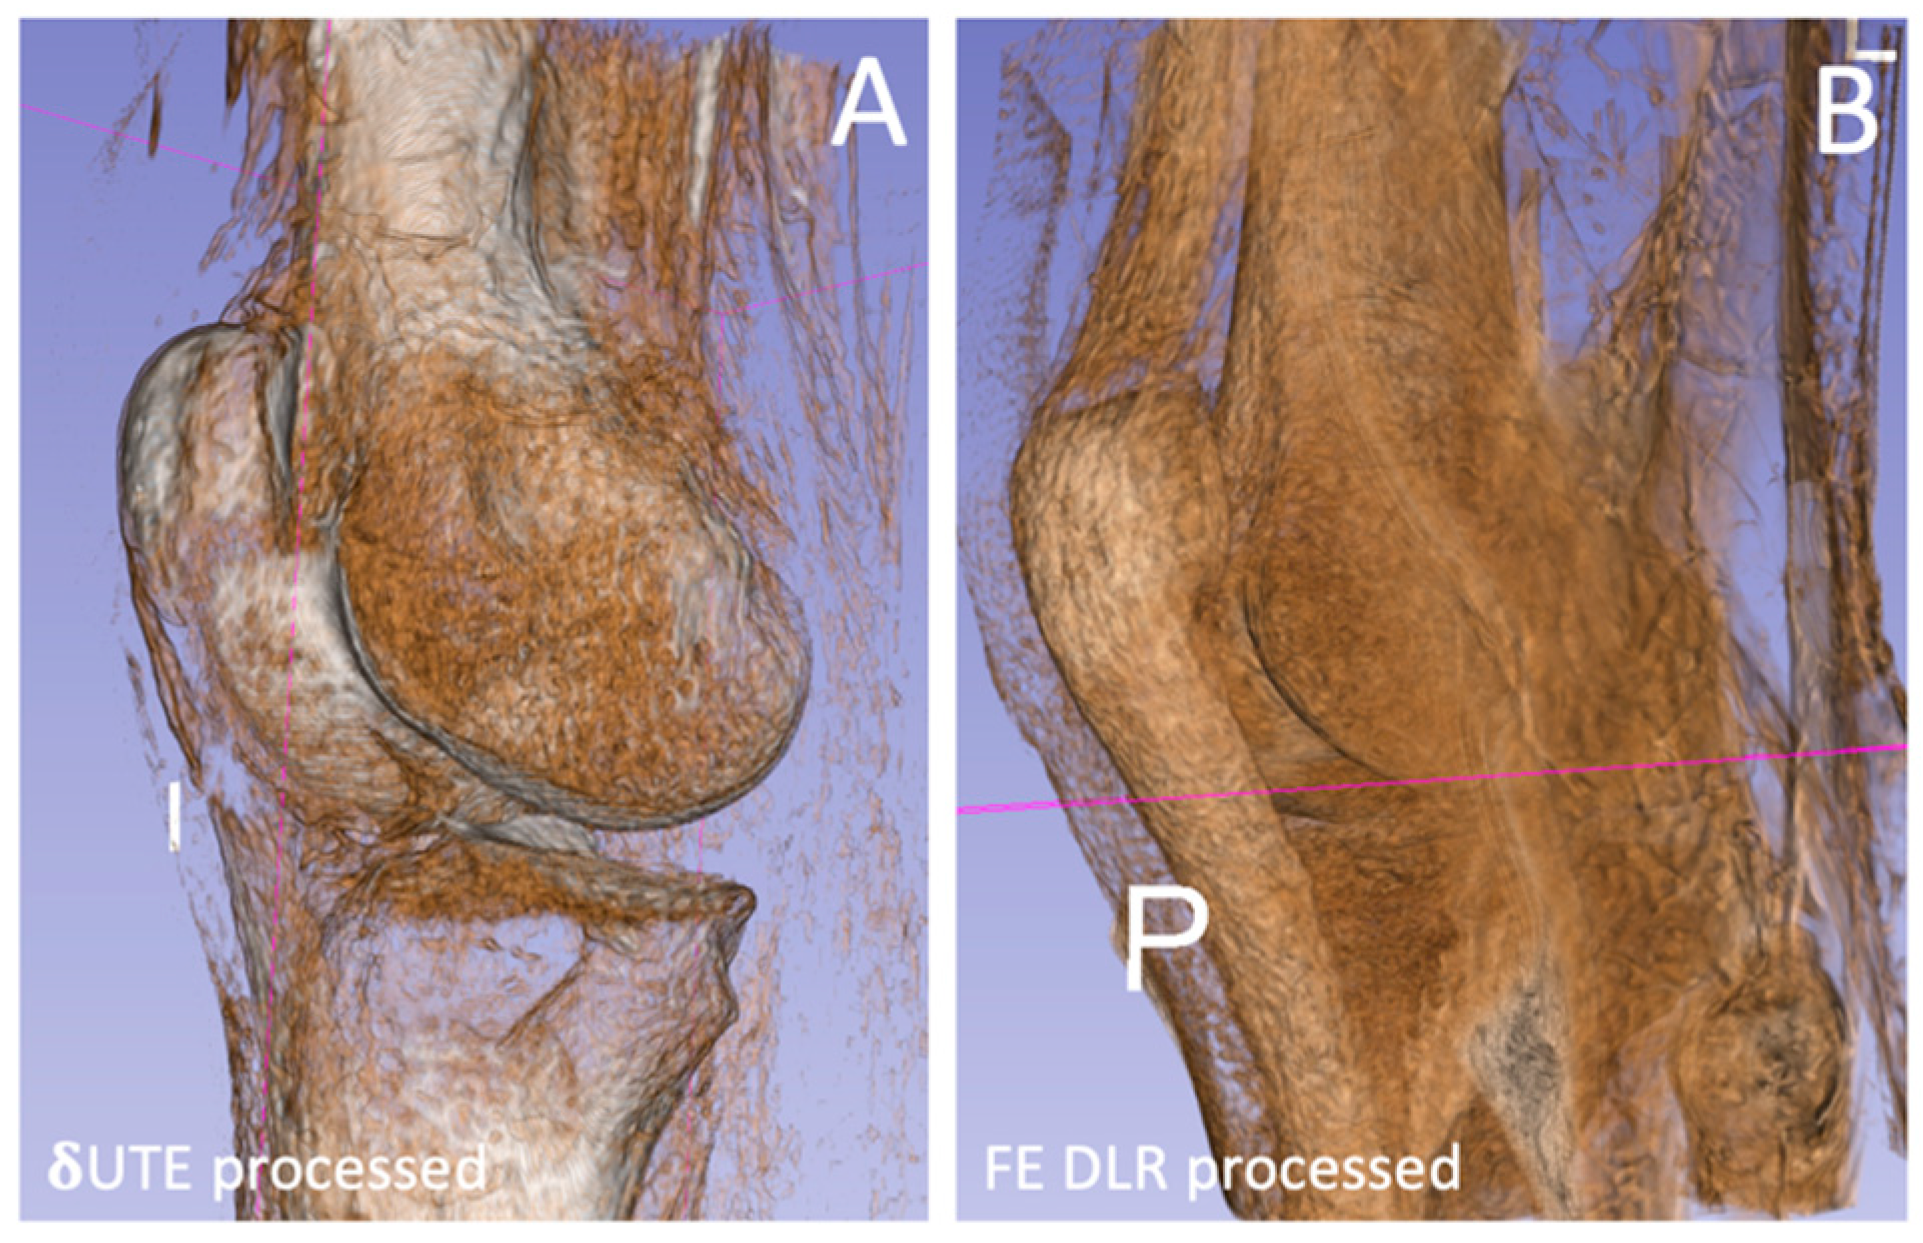

| Measurement | δUTE processed | FE processed | FE HR-DLR processed | p-value |

| Bone SNR | 104 (19.3) | 304 (271) | 410 (179) | 0.086 |

| Bone-Muscle CNR | 40.5 (8.4) | 187 (205) | 242 (139) | 0.137 |

| Bone-Cart CNR | 33.8 (6.6) | 138 (148) | 177 (103) | 0.124 |